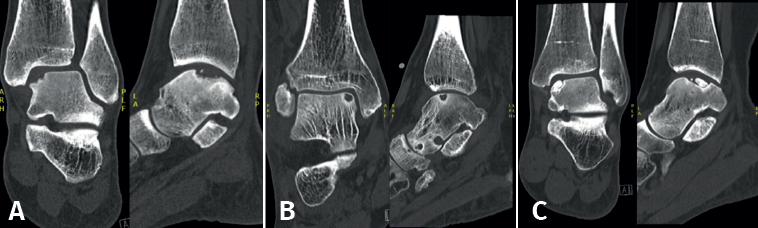

Lesions can be characterized by location, morphology, and size. Location can be described using a 9-grid anatomical scheme of the talus, as described by Raikin et al., shown in Figure 1(14). The morphology of OLTs can be described as crater-like, cystic, or fragmentary (Figure 2)(4,15,16). Lesion size should be reported in anterior-posterior plane, medial-lateral plane, and depth, allowing for calculation of lesion surface area and volume(4). However, there is no consensus on the reporting on morphology of OLTs, and while radiological classification systems for OLTs exist, they lack validation and utilize inconsistent terminology. Moreover, lesion size measurement methods vary, further contributing to inconsistency in lesion characterization in literature(15).

Retrograde drilling is a non-transarticular technique, using fluoroscopy for visualization of the talus, which allows for debridement and drilling of the subcartilaginous cyst. Retrograde drilling can be considered as a surgical intervention for cystic OLTs with an intact articulate cartilage layer(22). Retrograde drilling allows for the penetration of the necrotic sclerotic zone for bone marrow stimulation, without damaging the intact cartilage surface(37). Similar to BMS, retrograde drilling causes disruption of the intraosseous blood vessels and thereby promoting subarticular bone filling of the cyst. After exposing the talus using anteromedial and anterolateral portals, a Kirschner wire will be positioned under fluoroscopic control, transtalar from the opposite talar neck into the subchondral sclerotic zone(37).

As an additional procedure, the debrided cyst can be filled with cancellous bone, particularly for large lesions, since the insufficient stem cells in the subchondral bone in these cases lead to a lower likelihood of adequate regeneration of damaged cartilage and subchondral bone(22,38). For primary OLTs, retrograde drilling has a success rate between 68% and 100% and a complication rate of 5%(22,29).